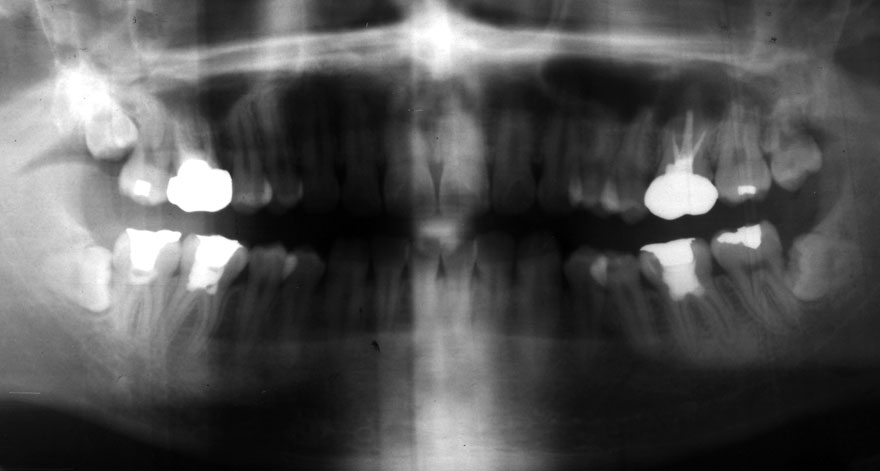

初診時 25歳 男性 平均歯槽骨喪失量:1.43mm

河田歯科医院

30年後 55歳

平均歯槽骨喪失量:1.56mm

22年間喪失量:-0.14mm

年間喪失速度:-0.005mm

(ケア頻度:4.21ヵ月ごと)

初診時 25歳 女性 平均歯槽骨喪失量:1.11mm

22年後 47歳

平均歯槽骨喪失量:1.31mm

22年間喪失量:-0.19mm

年間喪失速度:-0.009mm

(ケア頻度:2.35ヵ月ごと)